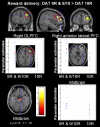

In humans, dopamine neurotransmission is influenced by functional polymorphisms in the dopamine transporter (DAT1) and catechol-O-methyltransferase (COMT) genes. Here, we used event-related functional magnetic resonance imaging to directly investigate the neurofunctional effects of the Val(158)Met COMT and variable number of tandem repeat DAT1 polymorphisms on distinct components of the reward system in humans. The results revealed a main effect of COMT genotype in the ventral striatum and lateral prefrontal cortex during reward anticipation (P < 0.001, uncorrected) and in the orbitofrontal cortex at the time of reward delivery (P < 0.005), met/met individuals exhibiting the highest activation. The main effect of DAT1 genotype was seen in robust blood-oxygen-level-dependent response differences in the caudate nucleus and ventral striatum during reward anticipation (P < 0.001) and in the lateral prefrontal cortex and midbrain at the time of reward delivery, with carriers of the DAT1 9-repeat allele showing the highest activity. Moreover, an interaction between the COMT and DAT1 genes was found in the ventral striatum and lateral prefrontal cortex during reward anticipation and in the lateral prefrontal and orbitofrontal cortices as well as in the midbrain at the time of reward delivery, with carriers of the DAT1 9-repeat allele and COMT met/met allele exhibiting the highest activation, presumably reflecting functional change consequent to higher synaptic dopamine availability. Taken together, these results indicate that genetically influenced variations in dopamine transmission modulate the response of brain regions involved in anticipation and reception of rewards and suggest that these responses may contribute to individual differences in reward-seeking behavior and in predisposition to neuropsychiatric disorders.